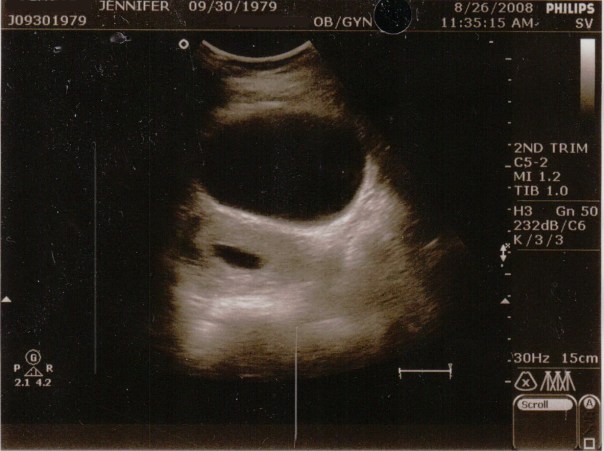

The first two images were during the regular abdominal ultrasound. The sac is the dark ovular hole on the left. The larger hole above it I believe is my bladder.

The next day by the time I was at the drs at 11:30am the bleeding had stopped entirely and my pad was completely clean. We went in for the ultrasound on Tuesday August 26 when I should have been 11 weeks 3 days along according to my LMP. I could barely move because I had to pee so bad so the tech told me she’d take a quick look and then have me empty. She did the abdominal ultrasound and said that I did a great job filling up my bladder (yippy, do I get a gold star?!), she pointed out the sac and said that we’d have to go internally to see the baby because it’s still so small.